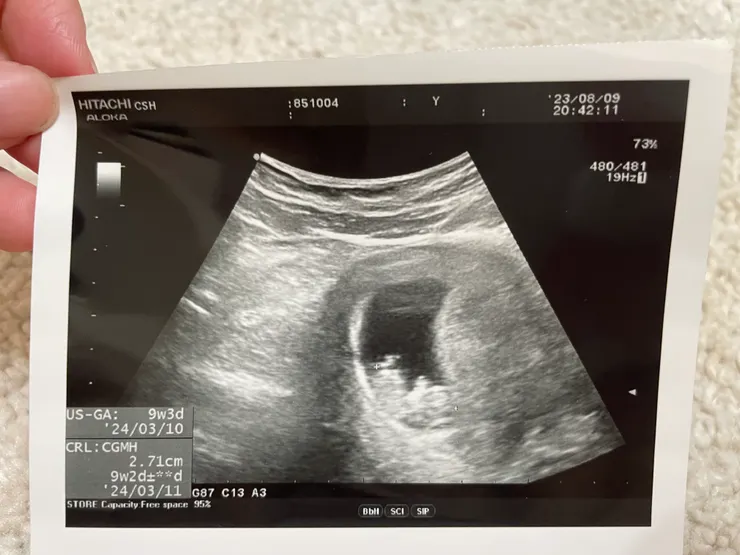

9W+2的小可愛

同週去看小福氣,小小心臟蹦蹦跳!讓媽媽我超開心~ 又度過了一回合!

這週他依然躺的亂七八糟,應該很舒服!